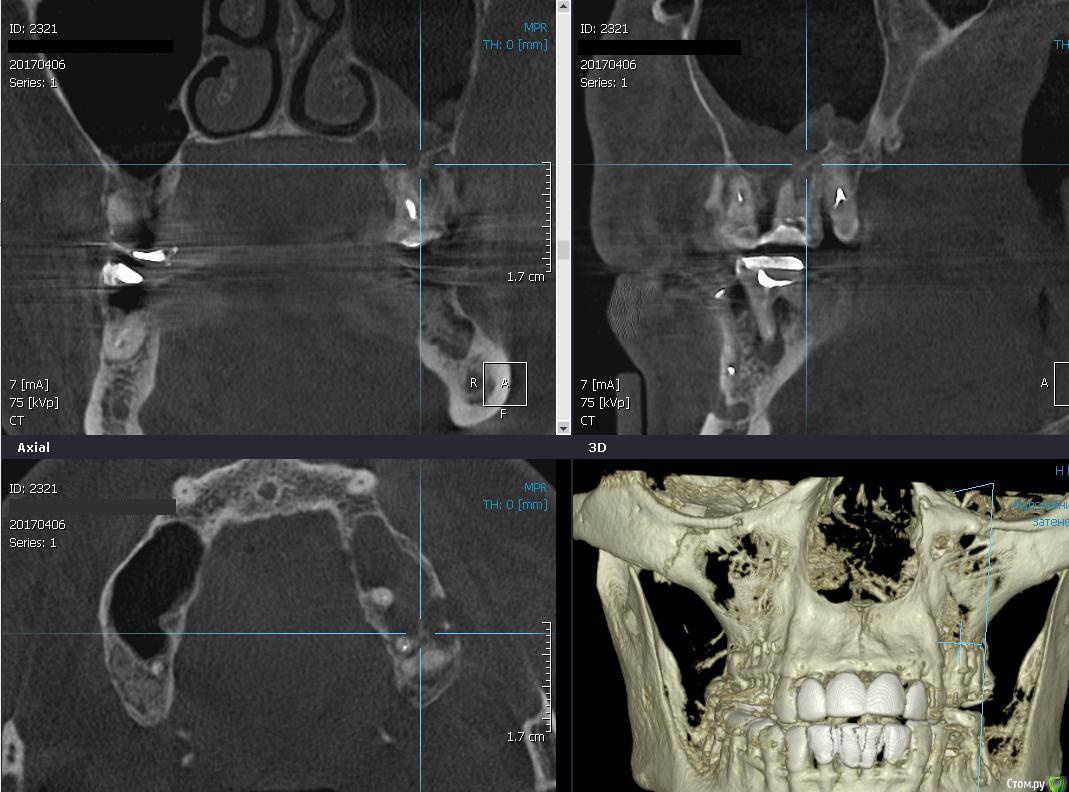

Romanson Опубликовано 10 апреля, 2017 Поделиться Опубликовано 10 апреля, 2017 Здравствуйте, подскажите как бы вы поступили в такой ситуации? Ничего не беспокоит, на затрудненное дыхание не жалуется.Удалить, отпустить, сделать повторное кт - если все нормально, то делать синуслифтинг, устанавливать имплантанты?Удалить, попытаться сделать пункцию мягкотканного компонента, если есть содержимое то пытаться вылущить оболочку из пазухи?Как действуете в подобных ситуациях? Ссылка на комментарий